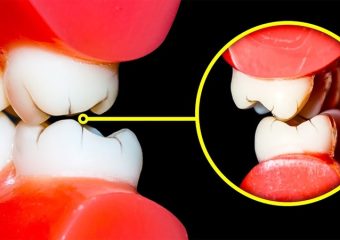

- دندانهای ساییده شده

- دندانهای شکسته یا ترک خورده

- ساییدگی مینای دندان، نمایان شدن عاج زیرین (داخل دندان)